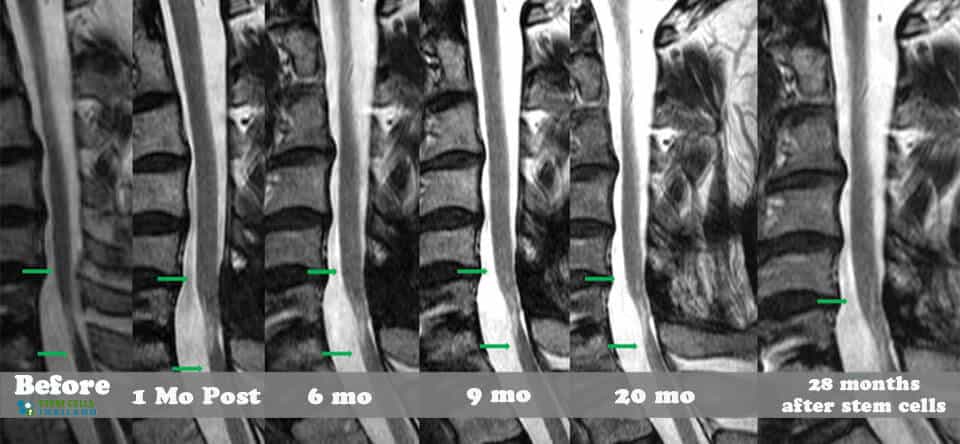

脊髓損傷的細胞療法側重于大腦和身體之間軸突的再生,這些軸突在事故發生后受到嚴重限制或不存在。我們針對脊髓損傷的干細胞移植可以幫助患者消除疼痛,恢復膀胱和腸道功能,恢復失去的感覺,并再生內臟運動神經元,同時最大限度地減少其他問題,例如損傷引起的痙攣或抑郁。傳統治療不解決再生問題,而是側重于疼痛管理、康復和減少繼發性損傷。

我們脊柱損傷治療中心的目標是幫助以自然和安全的方式修復損傷。我們的治療是在細胞水平上進行的,僅影響靠近影響點的區域。如果受傷時間不到兩年,積極的結果可能會非常顯著。對于那些患有老年損傷、創傷性腦損傷、嚴重椎間盤退變、股骨頭壞死、周圍神經病變或脊髓性肌肉萎縮的人來說,隨著時間的推移,完全康復的機會變得更加困難。

組織、軟骨或韌帶的新損傷對干細胞治療的反應要好得多。治療后的康復需要大量的奉獻和康復訓練。初次治療后約2-3個月,身體改善明顯,且效果是永久性的。[2]